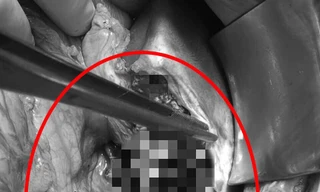

TPO - Bệnh nhân được đưa vào bệnh viện trong tình trạng sốc mất máu, giảm huyết áp, mạch tăng… Kết quả chụp CT Scan cho thấy bệnh nhân bị vỡ gan mức độ nặng, với gan trái gần như bị đứt lìa.

Bà Nguyễn Thị G (68 tuổi ở Thanh Xuân, Hà Nội) được đưa đến Bệnh viện Việt Đức cấp cứu trong tình trạng sốc nặng, suy hô hấp, tụt huyết áp do ngực phải bị biến dạng, bẹp dúm. Kết quả chiếu chụp cho thấy, bệnh nhân dập gãy nhiều xương sườn, dập nát phần mềm, tràn máu và khí màng phổi, vỡ gan...